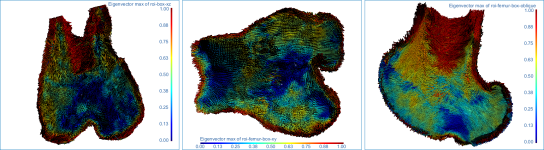

This section of the proximal femur tutorial describes how to compute high-resolution anisotropy maps in different orientations. You should note that when computing high-resolution maps, you should limit the volume of operation to regions that enclose only part of the region of interest. This can be done by creating a series of boxes that describe a particular orientation.

The images below (from left to right) correspond to XZ, XY, and oblique orientations. The computed vector fields are colored by magnitude.

High-definition vector field-based surface anisotropy maps

- Choose the settings for each high-definition vector field-based surface anisotropy maps on the Mappings tab, as shown below.

NOTE You can decrease the sampling spacing and radius of influence to 0.0005 m and 0.0015 m, respectively, since you will be computing maps within a sub-volume.